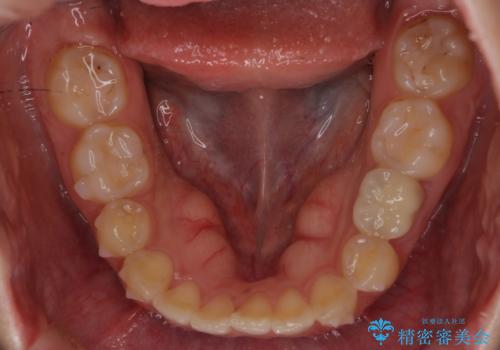

左下に乳歯が残っていましたが、被せ物に穴が空いている状態でした。

乳歯は抜かずに保存的な治療を行いました。

上下の正中が1本分ずれていましたが、ちょうど1本分で目立たず、また、右下の歯が生まれつき少ないことを利用して、最小限の歯の移動にとどめました。

乳歯はまだぐらついたりしていない状態だったため、しっかり虫歯を取り、根の治療も行いました。